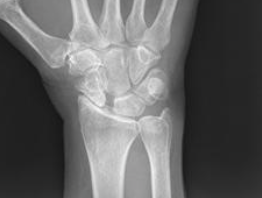

AP radiographs

Lateral

Chronic SL ligament injury-> DISI deformity

What is the classification system for SLAC & TX ?

WATSON

Stage 1- Arthritis between scaphoid & radial styloid

Stage 2- Arthritis of entire radioscaphoid joint

Stage 3- Arthritis between CAPITATE and LUNATE (pic)